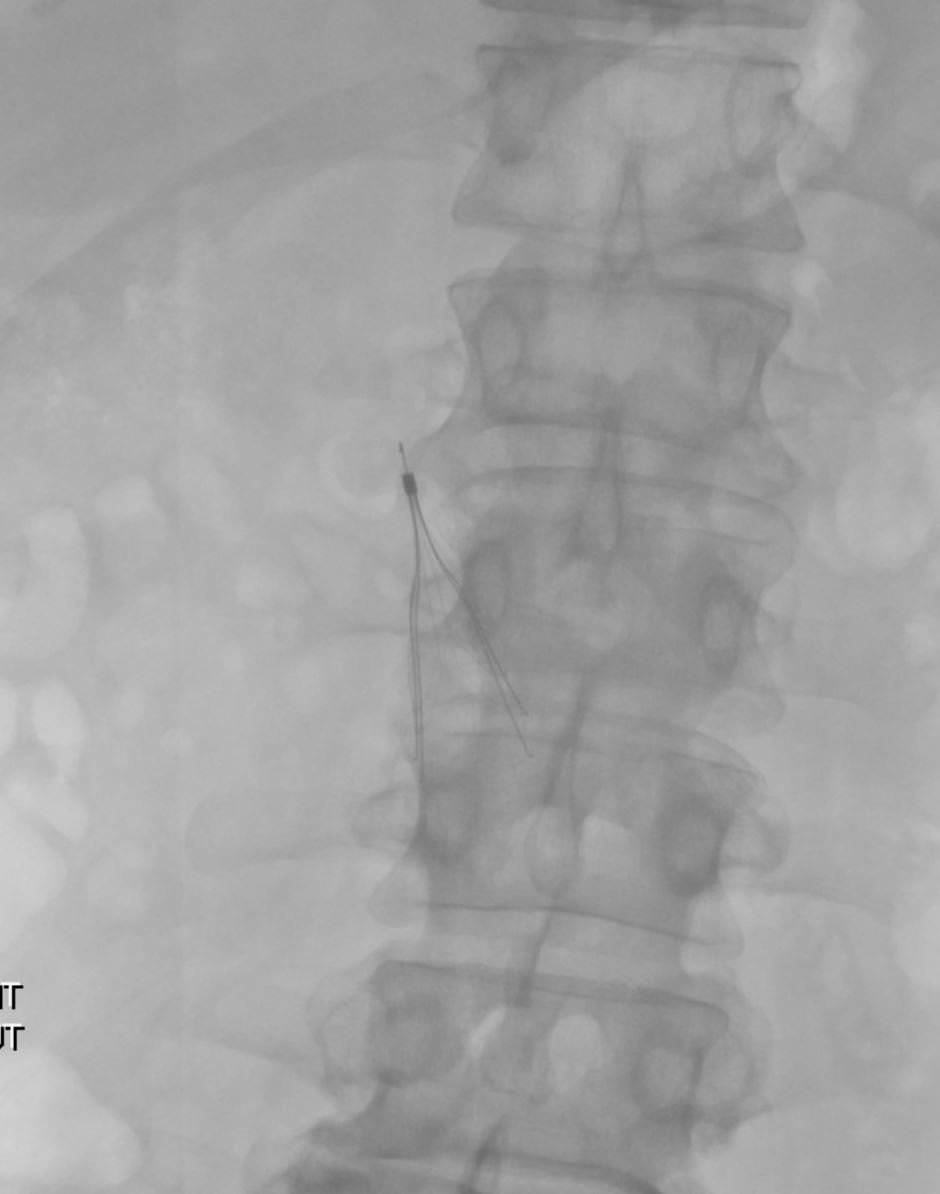

@kmadass

Filter Out Friday fun w/ @arslanmd @jtass6 @roshah31 5yr old embedded Venatech!! #laserlife #GTFO @rkryu @kush_r_desai @IvcFilterClinic